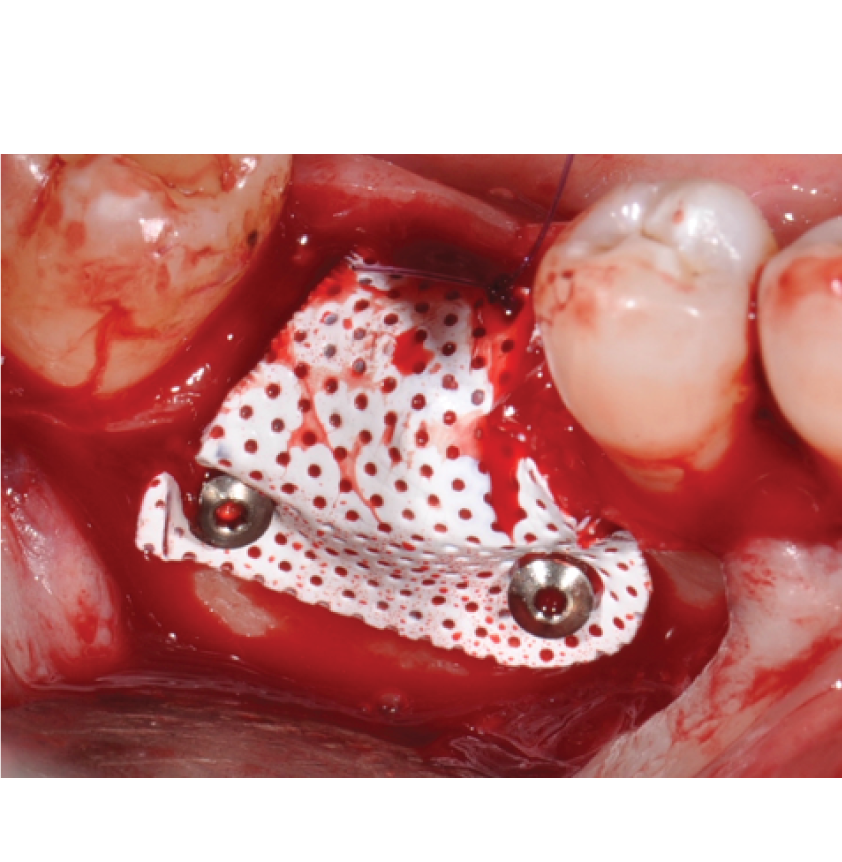

Director’s Clinical Cases

Director’s Clinical Cases

• Case presentations: Clinical pearl from real-world cases

• Case Presentations: Clinical Pearl and must-know takeaways